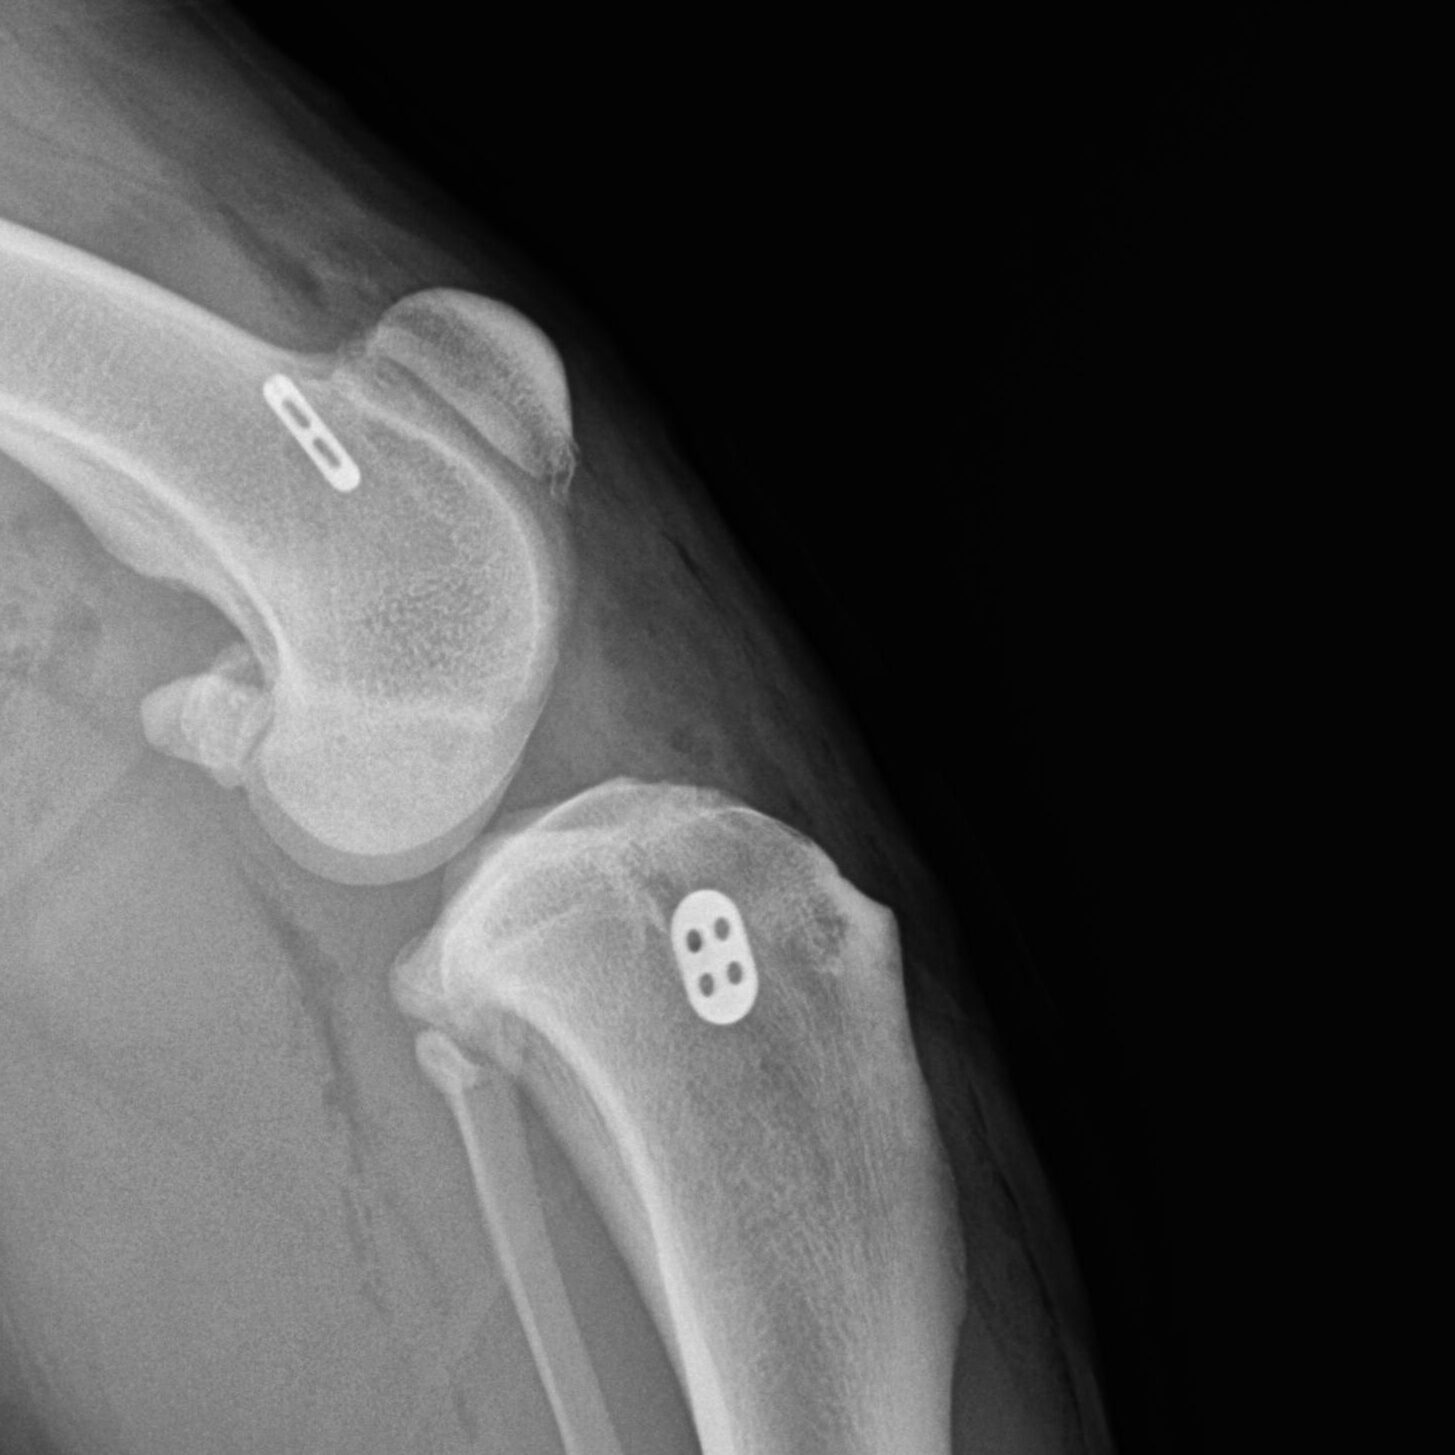

Knochenchirurgie

- Frakturversorgung, Korrekturosteotomie, u.a., verschiedenste Methoden wie Fixateur externe, interne Implantationen von Drähten, Nägeln, Schrauben, Platten inklusive SOP u.a.

Gelenkchirurgie inklusive Arthroskopie

- Kreuzbandriss, Meniskusläsionen, Patellaluxation, laxe Schulter, Isolierter Processus anconaeus, Fragmentierter Processus coronoideus, Osteochondrosis dissecans, Luxationen, Frakturen u.a.